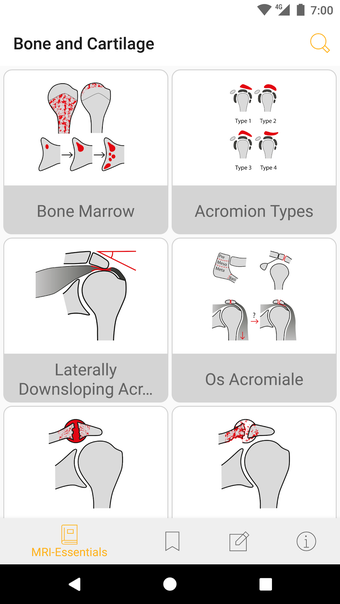

Jedes Thema wird in wenigen Seiten behandelt. Es gibt kurze Absätze mit einfachen Zeichnungen.

Die Basisversion liefert die wesentlichen Fakten, die immer noch kurz und prägnant sind. Die Fakten konzentrieren sich auf die klinisch relevanten Aspekte des Zustands des Patienten.